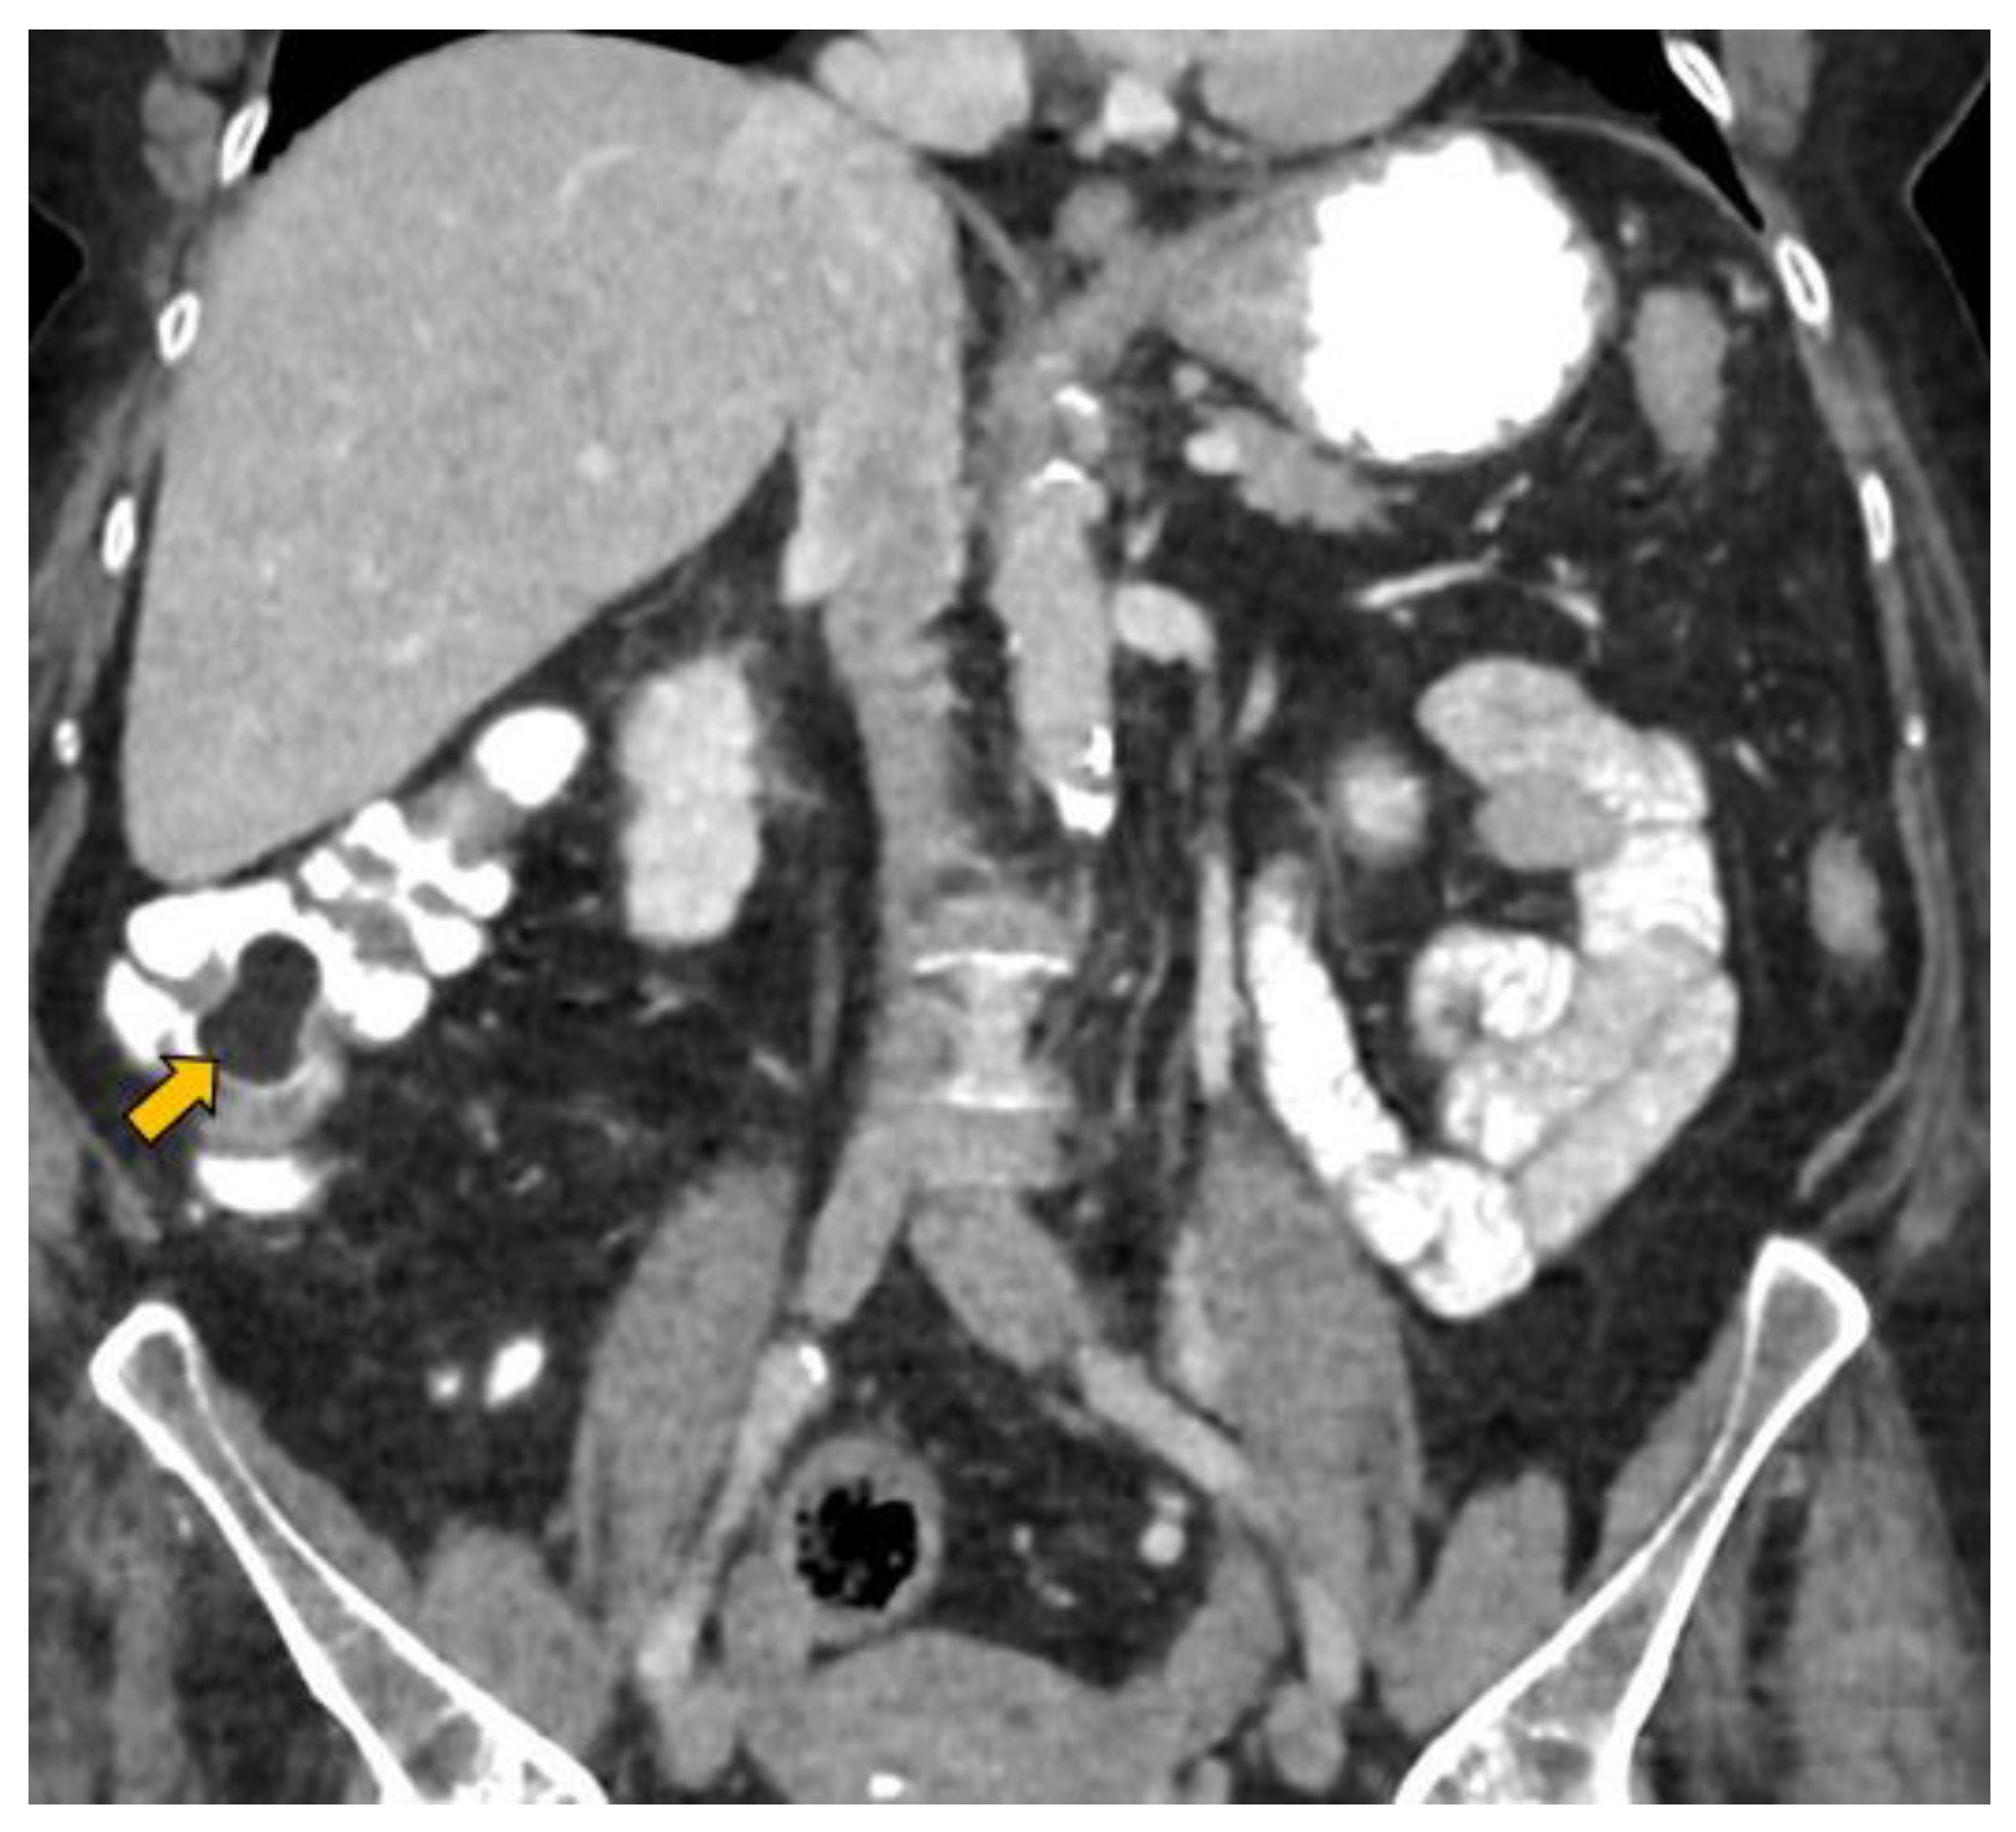

In our case, it was possible to follow up on the lipoma during biannual OCs performed because of her personal history of polyposis. Initially, it was proposed that abdominal-CT scans (Figure 1 and Figure 2) should be performed the year after each OC. This way, the size of the lesion could be monitored, and the degree of local infiltration could be determined. After the first abdominal-CT follow-up, to avoid exposure to radiation, HS (Figure 3) was included as an alternative to abdominal-CT. In the subsequent follow-up, in addition to the biannual OCs, two hydrocolonic ultrasound scans (without cleansing preparation) and one abdominal-CT scan were performed. During the seven years of follow-up, the lipoma remained stable, and the patient remains asymptomatic.

Figure 2.

Coronal CT reconstruction of the abdomen with intravenous and oral contrast showing the colonic lipoma (yellow arrow).

MR with fat saturation techniques can also be useful for detecting lipomas, but the detection of small lesions can be complicated [7]. The sensitivity of MR in the detection of fat composition is 100% [1]. Lipomas are easily distinguishable using abdominal-CT, as they appear as well-defined hypodense lesions between −40 and −120 Hounsfield units [36] (Figure 1 and Figure 2). The sensitivity of abdominal-CT in the detection of lipomas is 58–100%, and they have a characteristic image that looks like a “target sign” or “doughnut sign” [5,37]. Abdominal-CT is a very useful technique in urgent cases, but for follow-up, it presents problems due to the associated radiation. In addition, local infiltration can be difficult to exclude using abdominal-CT or MR [1].